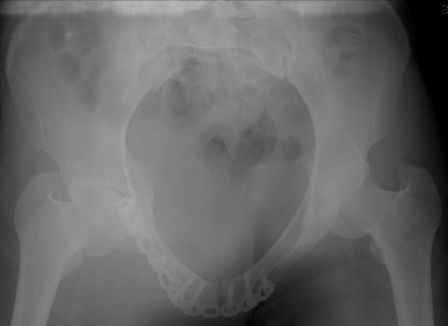

Re: перелом таза

Серия до- и послеоперационных снимков этой пациентки. Хотя бы post factum обсудить. Не знаю, что можно сделать с задними отделами стержневым аппаратом, но три крепких парня открытым путем с помощью "волшебных" слов еле-еле смогли отрепонировать - сзади все было очень ригидно!